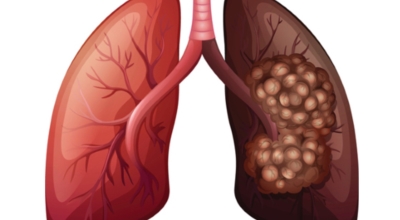

폐암에 대해서

폐에 발생된 악성 종양을 말하며 오랜 기간 흡연해온 남성들에서 발병률이 높고 요즘 들어 가지가지 환경적인 요인의 영향과 간접흡연으로 흡연하지 않는 여성에서도 많이 발생하고 있어요. 증상을 느껴 병원을 찾았을 때는 수술하기 늦은 경우가 많아 사망하는 비율이 매우 높은 암입니다.

폐 자체에서 생기거나 다른 장기에서 발생된 암이 폐로 전이되어 나타나기도 하고 특별한 초기 증상이 없는 경우가 많다고 하며 암이 진행된 후에도 일반적인 감기 증상인 기침과 가래 외의 특이 증상이 나타나지않아 증상만으로는 진단이 쉽지 않아요. 폐암 역시 다른 암들과 마찬가지로 조기 발견 및 치료가 매우 중요하므로 일상 속에서 폐암 초기증상을 간과하지 않도록 주의를 기울여야 해요.